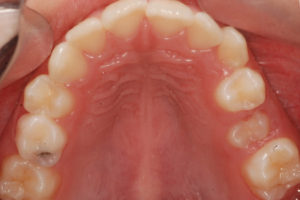

Documento utilizado en todo procedimiento odontológico y en cualquier especialidad, consiste en una secuencia de fotos faciales y dentales en diferentes ángulos, que permiten un diagnostico ideal y evaluar los avances del tratamiento al tener fotos posteriores, además es un documento legal.